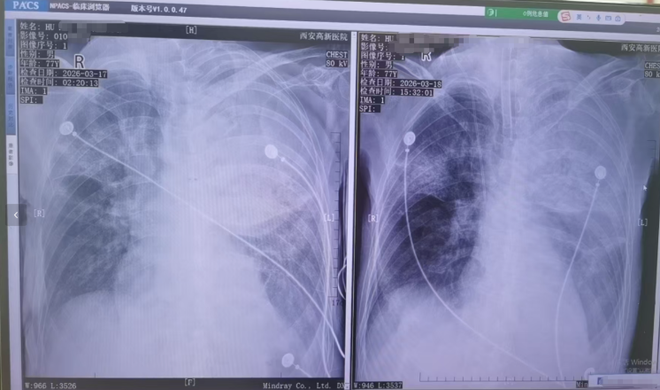

胡先生说,起初以为是感冒,住院治疗没有效果,还越来越严重,以至于病情危重,“整个肺部全白了”,并且出现呼吸衰竭,医院甚至下了病危通知书。3月17日,家人赶紧将父亲转院到西安高新医院抢救,到医院以后就住进了ICU。经检查,才发现是鹦鹉热衣原体感染导致的重症肺炎。胡先生提供的一份《西安高新医院诊断证明》显示,胡先生的父亲3月17日以重度肺炎入院。诊断为重症肺炎(鹦鹉热衣原体感染)I型呼吸衰竭,急性呼吸窘迫综合征,脓毒症等。

患者胸片